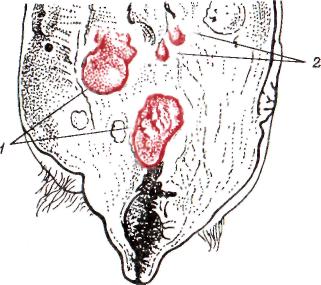

Абсцессы вымени (Absces-sus uberis). Если микробы распространяются по молочным ходам или гематогенным путем, в вымени появляется большое количество гнойников величиной от просяного зерна до горошины (рис. 2). Они или рассеиваются по пораженной доле вымени, или группируются в одном или нескольких его участках (Mastitis purulenta disseminata). Увеличиваясь до размера грецкого ореха и больше, они расплавляют паренхиму вымени, сливаются между собой и образуют более или менее значительной величины абсцессы (Abscessus uberis).

Рис. 2. Гнойный мастит: 1 - абсцессы; 2 – рассеянные. .гнойники